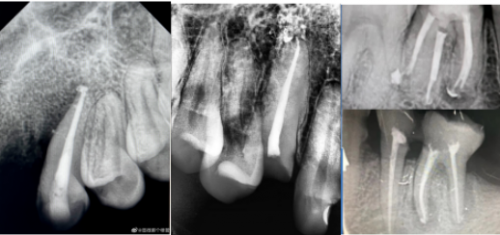

目前,赛濡特已收到数万个口腔医生成功完美的充填案例,有图有真相,图片是世界性的语言,专业医生一看就懂——

无与伦比的流动性C-RootSP充填很丝滑!

封闭性好:C-RootSP能进入牙本质小管内,生成羟基磷灰石,实现根管再矿化。

侧枝好充填,到达根管每一处微米根尖区域

生物相容性好,术后反应小,患者无感。

根尖周愈合快,充填长期效果显著。